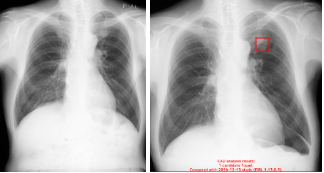

【解析結果の例】(3)

左:患者Aの、過去に解析したX線検査画像

右:患者Aの、新たに解析したX線検査画像

過去検出結果比較機能とは、本ソフトウェアが解析した胸部X線画像の画像情報を保持しておき、後日同一患者の画像を解析した際、過去の検出結果と比較することで、異常陰影候補領域の経時的変化(新規検出の有無)を表示する機能です。過去に検出されていない異常陰影候補領域が新規に検出された場合、二重線で表示します。(2)

(2)過去の画像と同一部位に異常陰影候補領域の検出があった場合は、単線で表示されます。

(3)画像はイメージです。